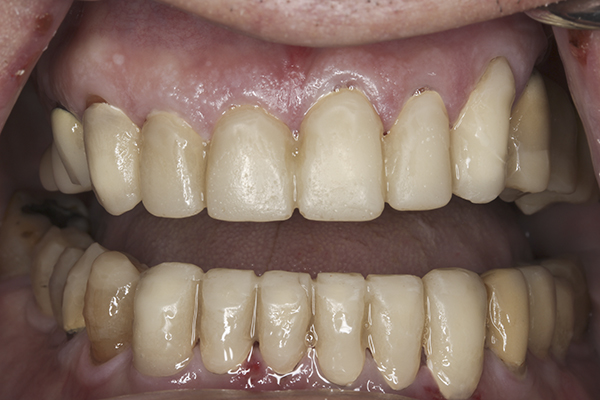

(10.) Preoperative anterior, closed view. Note the end-to-end occlusion of the anterior teeth and the wear on the incisors and centrals resulting in no anterior or canine guidance.

Figure 10